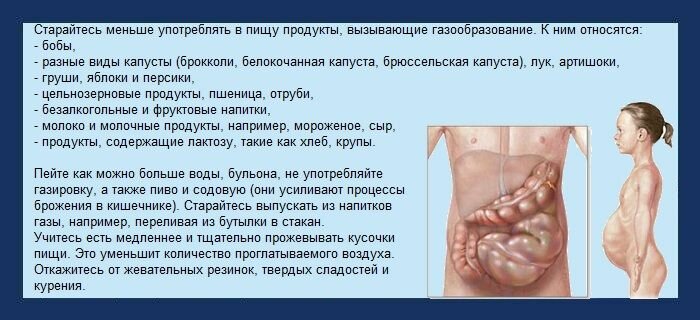

Вздутие живота – неприятное явление, которое периодами беспокоит каждого. Основные си Далее...

Метеоризм или вздутие кишечника давно обозначено врачами не как отдельное заболевание Далее...